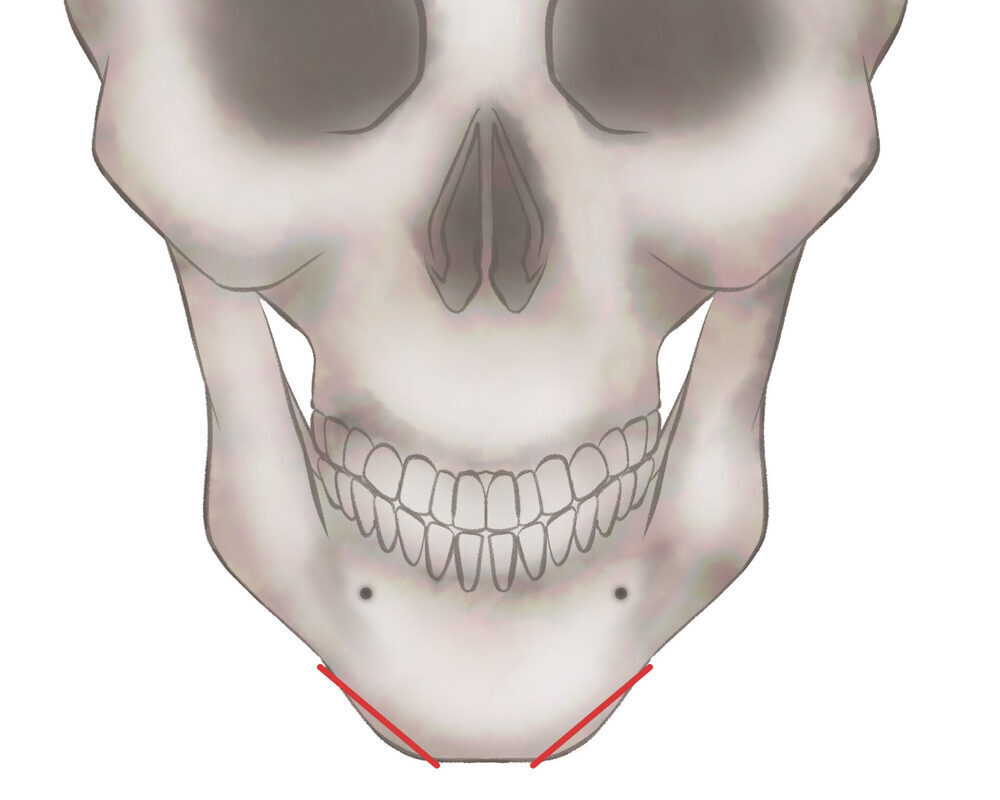

オトガイ骨切り(中抜き)

1.切開線をデザインします

2.骨を切除します

3.骨を移動させ段差を削ります

4.プレートで固定します